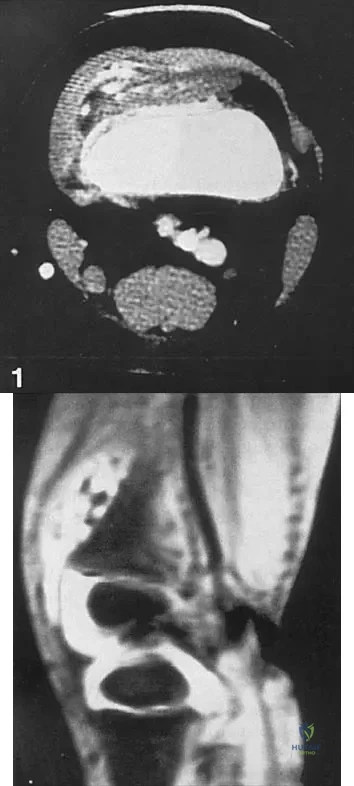

A 47-year-old woman has had left medial clavicle pain for the past 6 months. History is remarkable for mediastinal non-Hodgkin's lymphoma, treated with mantel radiation 22 years ago. A radiograph, CT scan, MRI scan, and a biopsy specimen are shown in Figures 68a through 68d. What is the most likely diagnosis?

Explanation